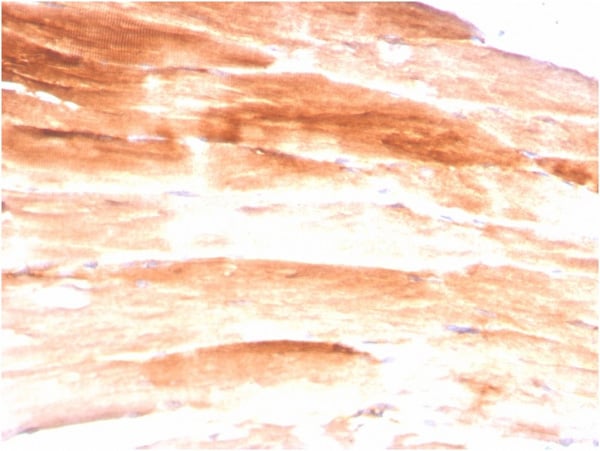

IHC (Immunohistochemistry)

(Formalin-fixed, paraffin-embedded human Skeletal Muscle stained with Dystrophin Monospecific Mouse Monoclonal Antibody (DMD/3245).)